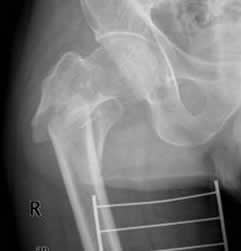

Fig 42. Angulación en varo.

Rx AP. Fractura subtrocantérica de la cabeza femoral, con desviación medial del fragmento distal.